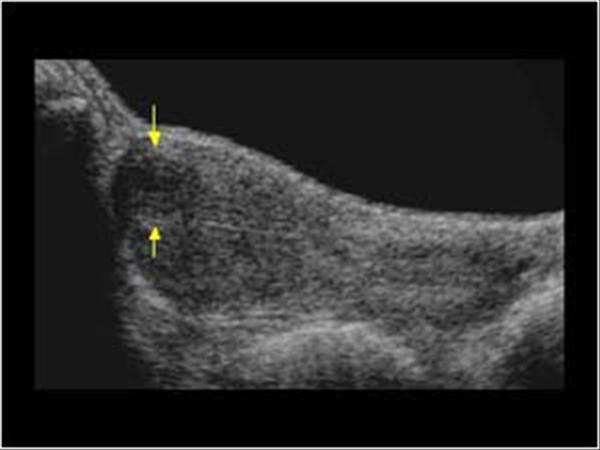

5) Tanı: Hangi Testler Gerekebilir?

• Transvajinal ultrason: İlk değerlendirme.

• SIS (salin sonohisterografi): Kavite konturunu netleştirir.